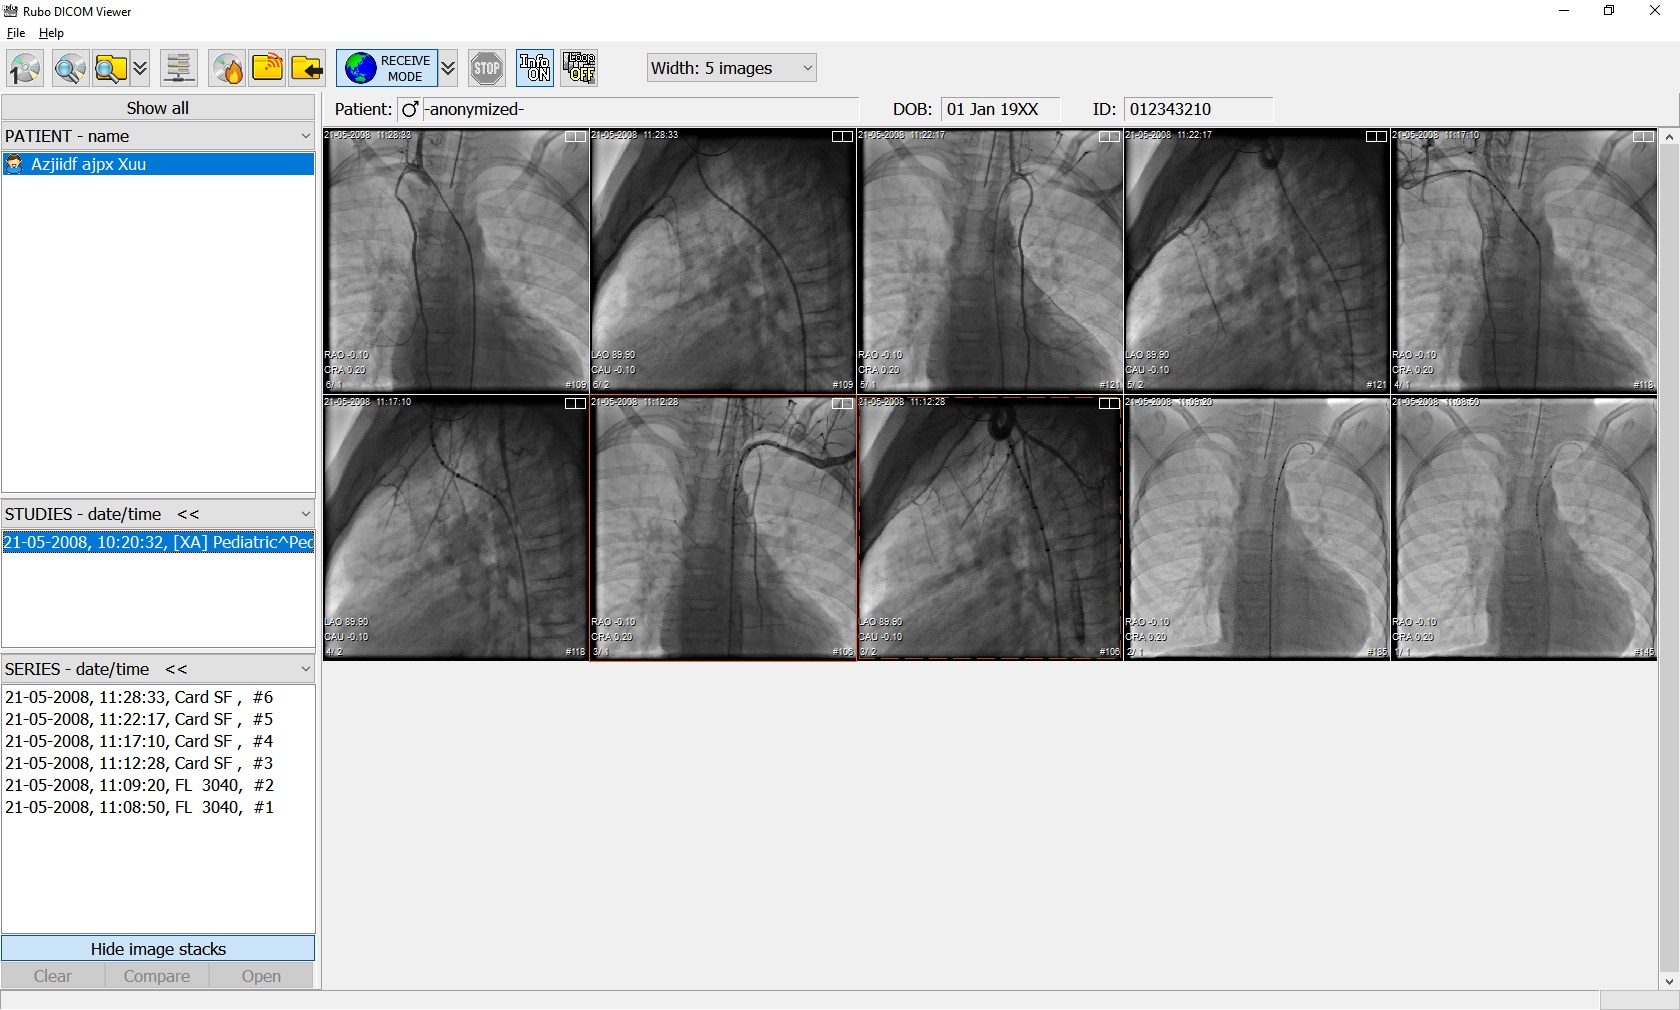

Лазерная камера сетевая для печати изображений на пленке стандарт dicom